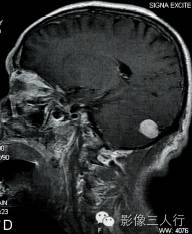

A.T2WI横断面;B.T1WI横断面;C、D、E.增强横断面、矢状面、冠状面;F.HE×100

图A、B:平扫MRI显示右侧小脑后缘类圆形结节状病灶,大小约1.4cm×2.0cm×1.8cm,在T2WI呈稍高信号,T1WI为稍低信号,边界清楚,信号均匀,局部脑组织受压内移。图C~E:Gd-DTPA增强扫描显示结节呈较均匀明显强化,病灶边缘清楚,其中在横轴位图像显示肿瘤中央部分强化较周围明显,且类似日光放射状。矢状位、冠状位图像见肿块强化变均匀一致,紧贴小脑后方硬脑膜或颅骨,但未见明显硬脑膜尾征。